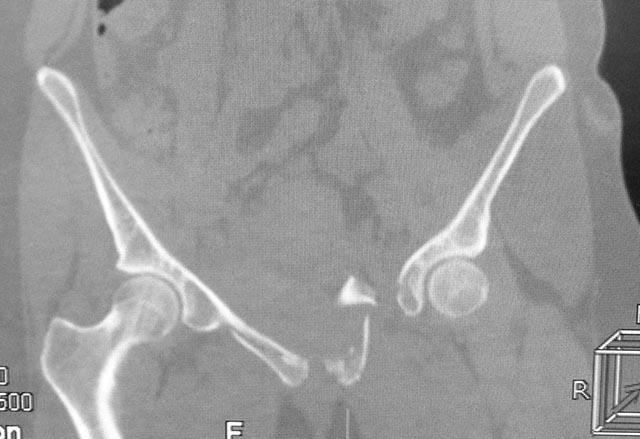

Женщина,21, социальна, без вредных превычек, сбита авто.

Кожа не повреждена. Других повреждений нет. Гемодинамически стабильна. травме 2 сут. Планируем спереди открыто через Stoppa, далее сзади крестец и ость закрыто (крестец может через обе массы?). Интересует мнение по альтернативным вариантам и по предложенному (tricks and shots). Заранее благодарен.

PS Только часть скринов с body scan, один с контрастированием пузыря.